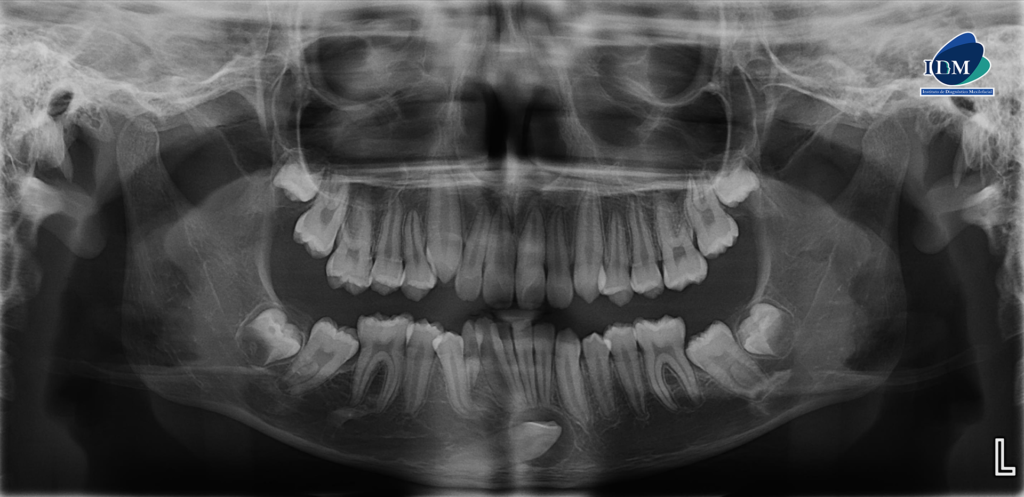

En la radiografía panorámica (Figura 1), se observa pieza 83 en persistencia; pieza 43 retenida, mesioangulada y proyectada en sínfisis mandibular, además se observó una imagen radiolúcida pericoronaria redondeada, de limites definidos y bordes corticalizados. Así mismo la pieza 48 se encontraba en evolución intraósea con presencia de imagen radiolúcida definida ubicada por debajo del limite amelodentinario.

Radiografia Panorámica